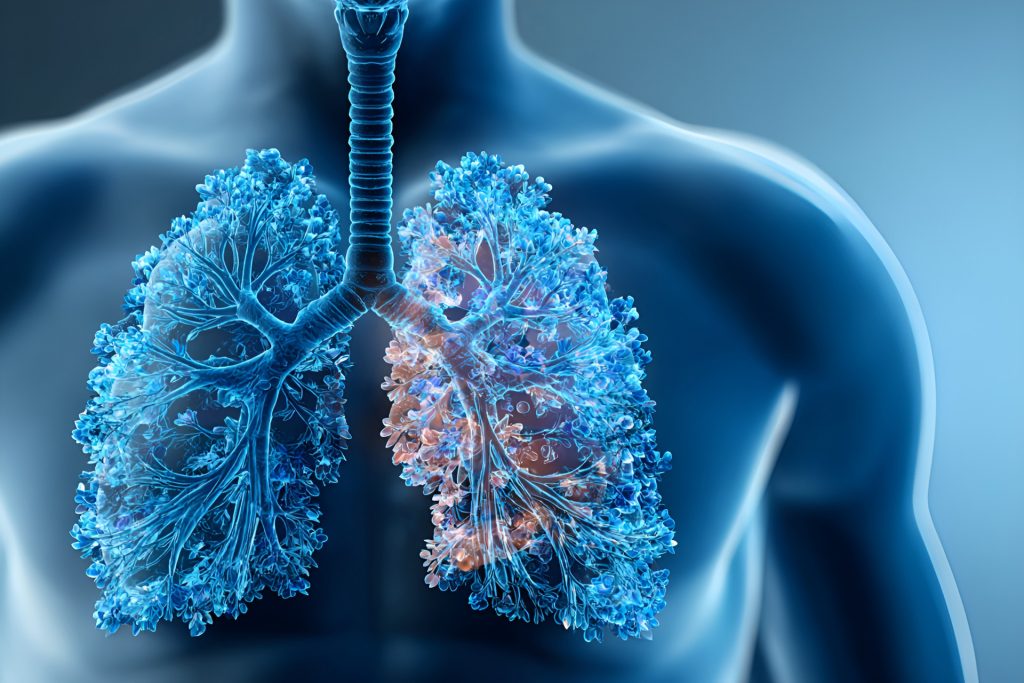

低剂量肺结节CT筛查

影和医学影像通过KARL 3D迭代重建技术,超低剂量(10mAs)高清成像扫描,更适用于筛查与随访。目前公认的早期肺部筛查先进手段,对>3mm结节秒检出,让肺癌的种子无所遁形

核心筛查价值:

本方案采用国际公认的低剂量螺旋CT技术,在保证图像质量的同时显著降低辐射暴露,能早期发现:

微小结节(直径3mm以上即可检出)

病毒性肺炎及各类肺部感染

早期肺肿瘤及其他占位性病变

AI评估报告的四大优势:

对于检出的肺结节,AI智能报告提供:

精准量化:自动测量结节直径、体积,计算倍增时间

三维可视化定位:立体呈现结节位置及与周围血管关系

影像组学分析:提取百余项影像特征,辅助评估良恶性风险

个性化管理方案:根据结节特征提供分级随访建议及健康指导